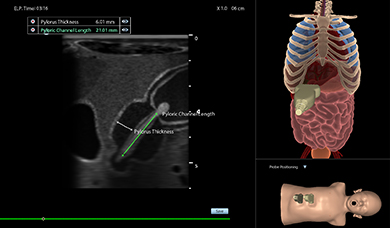

Simbionix Ultrasound Mentor is the answer to the growing need for ultrasound training among multiple medical specialties. This modular simulation platform enables easy manikin rotation (male, female, pediatric and interventional), and offers diverse applications for a range of specialties such as OB/GYN, Point-of-care Ultrasound (POCUS) and Echocardiography.

Ultrasound Mentor accelerates the development of basic to advanced technical and cognitive skills, by providing not only the probe manipulation training, but also a didactic environment enabling structured, self-guided learning including step-by-step instructions and educational aids such as 3D anatomical map and probe positioning assistant, all backed up with our progress monitoring tool MentorLearn.

- Advanced diagnostic tools, including Color Doppler, CW, PW, M-mode, and measurements

Advanced Abdominal Module

Pediatric Abdominal Module